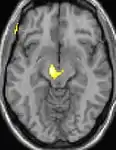

Positron emission tomography (PET) scans indicate the brain areas which are activated during attack only, compared to pain free periods. These pictures show brain areas that are active during pain in yellow/orange color (called "pain matrix"). The area in the center (in all three views) is specifically activated during CH only. The bottom row voxel-based morphometry (VBM) shows structural brain differences between individuals with and without CH; only a portion of the hypothalamus is different.[37]